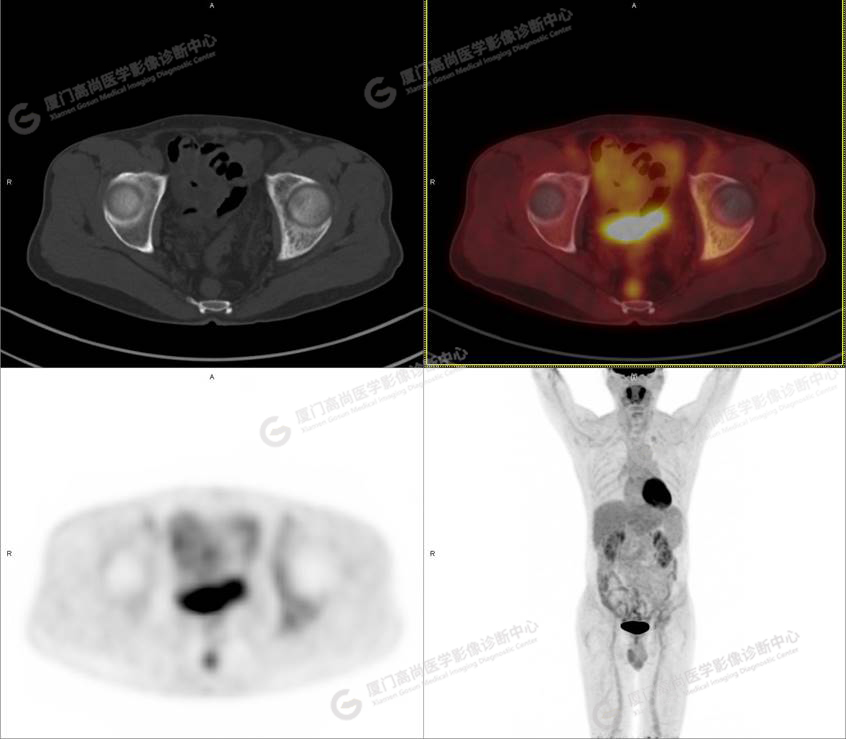

病史摘要1

60歲的L先生,因“左側(cè)臀部疼痛伴行走困難3月余”就診,外院核素骨顯像示:左側(cè)髂骨顯像劑增加,考慮惡性病變可能。同時實驗室檢查發(fā)現(xiàn)腫瘤指標(biāo)糖類抗原724稍增高。談癌色變!驚恐的L先生選擇了腫瘤檢查的核武器——PET/CT以探明虛實。

PET/CT檢查

PET/CT所見:左側(cè)髂骨、髖臼及恥骨骨質(zhì)密度不均勻增高,CT值約594Hu,邊緣模糊,放射性攝取輕度增高,SUVmax 2.79,周圍軟組織未見明顯異常。

影像診斷: L先生和Z女士的骨骼改變,指向了同一個疾?。汗抢w維異常增殖癥。